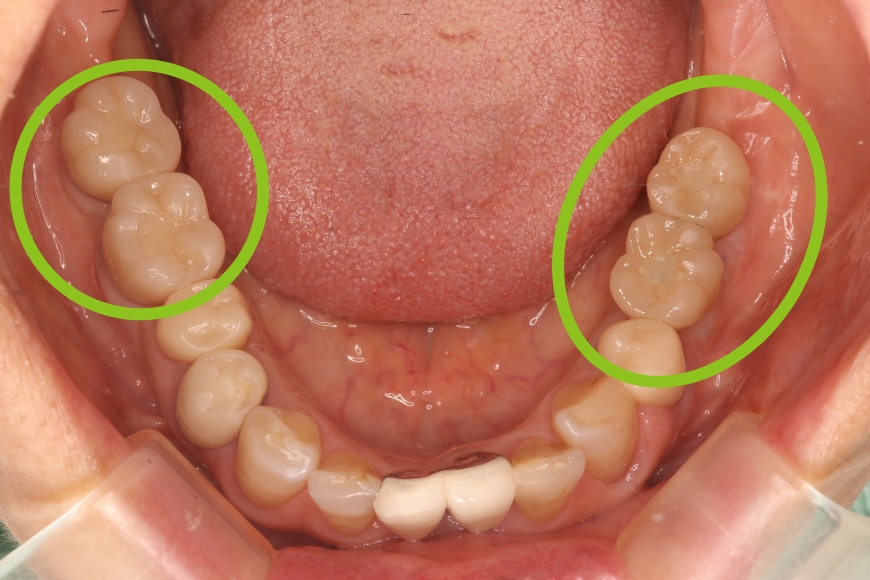

50代女性 左右の奥歯へのインプラント治療

治療前

治療後

治療内容 下の左右の奥歯が無く、食事がうまくできないことを主訴に来院されました。

左右の奥歯に2本ずつインプラント治療を行いました。奥歯でしっかりと噛めるようになりました。

治療期間・回数 治療期間:約6ヶ月

通院回数:10回程度

1,760,000

(1本440,000円×4本分。時期や手法により異なる場合があります。)

副作用・リスク ・インプラント埋入手術直後は、不快感、痛みを感じることがあります。

・下顎のインプラントは下歯槽神経に障害を及ぼした場合、数か月の知覚異常が生じる場合があります。

・インプラント周囲炎(インプラントの歯周病)などのトラブルを防ぐため、定期的なメンテナンスを行う必要があります。